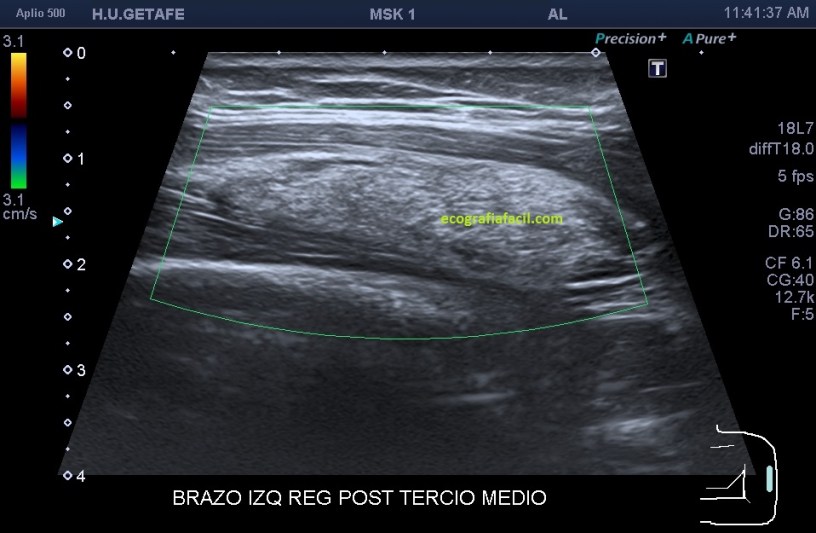

Si está por debajo, es decir, en el músculo como es en este Caso 3 que ves a continuación, la transmisión del sonido y la visualización del lipoma podrían serán peores, son los conocidos como lipomas intramusculares…mira el caso que te presento a continuación:

Como ves en este tercer caso del Post, es una mujer con un bulto en el brazo, en la localización que marcan las imágenes. El aspecto es hiperecogénico, respecto del músculo que lo envuelve que como muy bien sabes es hipoecogénico por definición. Los márgenes están marcados y definidos y el lipoma intramuscular está perfectamente localizable dentro del músculo. Su aspecto ecogénico es ligeramente heterogéneo. No tiene vascularización. Para ser un lipoma intramuscular se ve muy bien ya que está situado en una extremidad, como he mencionado anteriormente, en la cintura escapular o en paravertebrales que suelen ser habituales estos lipomas intramusculares, su visualización será un poco difícil, por la mala transmisión.

Observa la imagen 12 y 13, que son la misma, para que veas cómo se sitúa el lipoma dentro del músculo, y sus márgenes, luego para que veas la ecoanatomía de la imagen. El protocolo de estudio es el mismo siempre, localización, medición, vascularización.